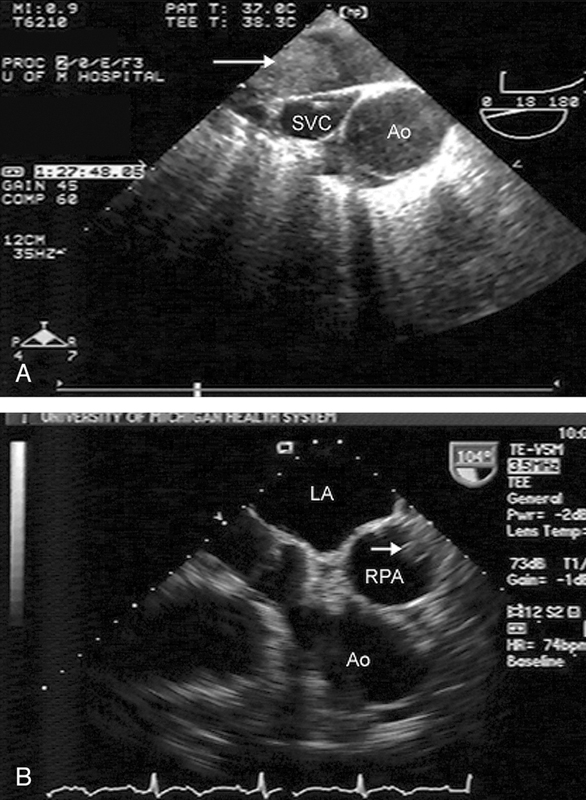

فحوصات تشخيصية لبعض امراض القلب والشرايين التاجية